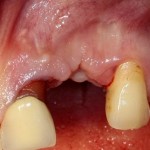

Около трёх лет назад к нам в клинику обратилась пациентка Мария, на момент обращения ей было 45 лет. Её беспокоила ситуация с передними резцами:

В ходе беседы она рассказала, что лечит эти зубы всю сознательную жизнь — их депульпировали («удалили нерв») из-за последствий травмы еще в школьном возрасте, и после этого каждые несколько лет (а то и чаще) ей приходилось перелечивать каналы, менять коронки, вкладки и т. д.

В результате, зубы приобрели очень уж нездоровый вид (см. фото выше). Вдобавок, всё усугубилось существенным снижением качества жизни — коронки и вкладки из зубов постоянно выпадают, десна вокруг них кровоточит при чистке…. Кроме того, Марию не покидает ощущение того, что эти зубы могут просто вывалиться в самый неподходящий момент. Именно это заставило её обратиться в нашу клинику.